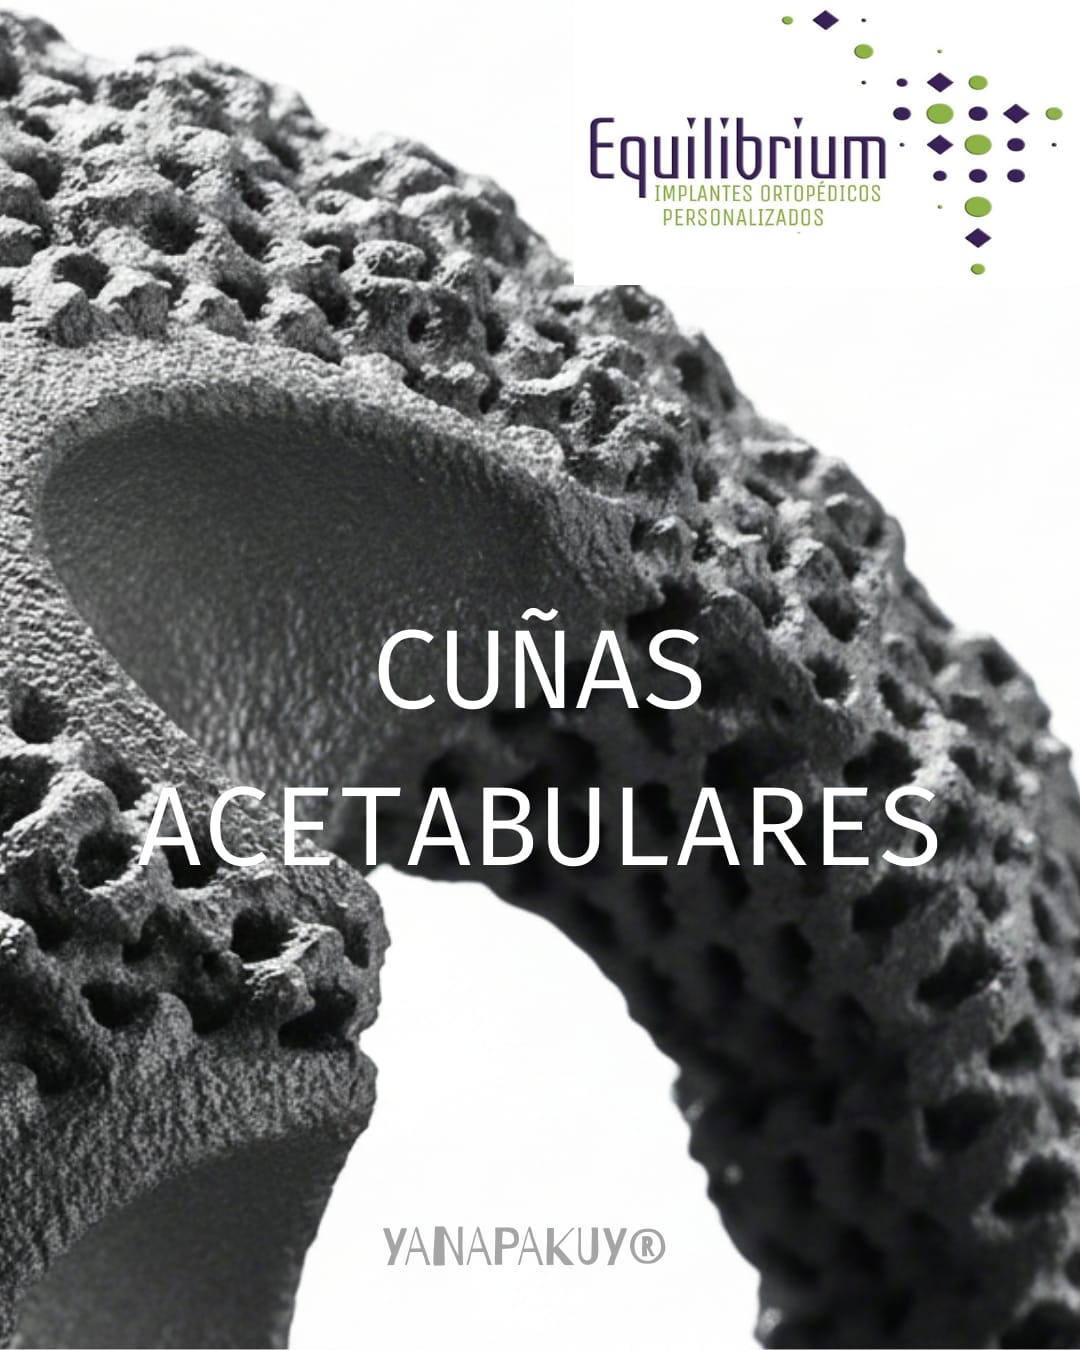

Titanio Trabecular

Reproducimos en nuestros implantes de titanio trabecular biocompatible la misma trama de cavidades que posee el hueso humano, logrando implantes livianos, altamente resistentes y con excelente integración ósea.